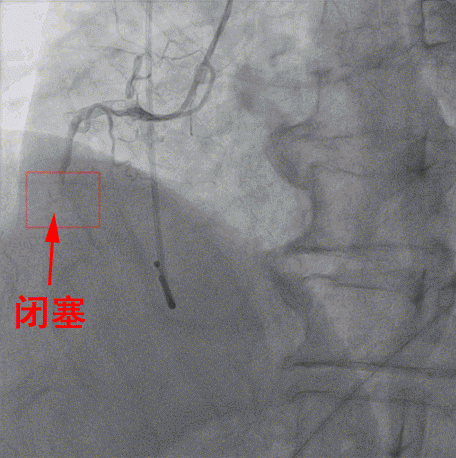

随後患者被迅速送進介入手術室,行右冠狀動脈支架手術,手術由内一科(心内)馬澤洪醫生等實施。經DSA引導下冠狀動脈造影顯示,患者右冠狀動脈近端完全閉塞,意味着右冠脈無法供血給心肌,心肌大面積處于嚴重缺血、缺氧的瀕死狀态。